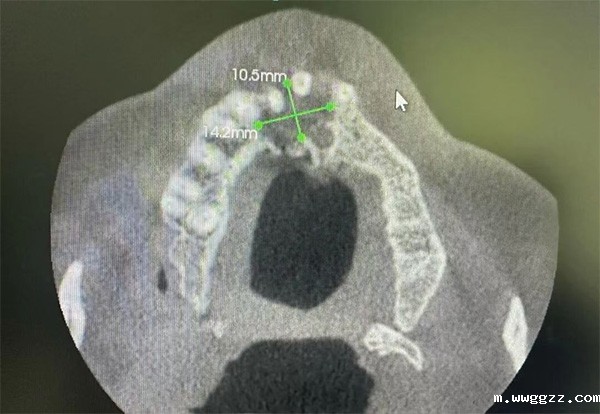

本例患者为54岁男性,因“外伤致11牙松动2个月”就诊。CBCT影像显示:11牙根中下1/3处见横向折断线,周围牙槽骨高度及宽度条件尚可,具备即刻种植的解剖基础。